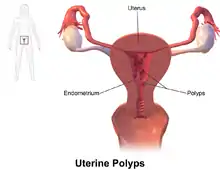

| Endometrial polyp | |

| Other names | Uterine polyp |

An endometrial polyp or uterine polyp is a mass in the inner lining of the uterus.[1] They may have a large flat base (sessile) or be attached to the uterus by an elongated pedicle (pedunculated).[2][3] Pedunculated polyps are more common than sessile ones.[4] They range in size from a few millimeters to several centimeters.[3] If pedunculated, they can protrude through the cervix into the vagina.[2][5] Small blood vessels may be present, particularly in large polyps.[2]

Endometrial polyps can be solitary or occur with others.[11] They are round or oval and measure between a few millimeters and several centimeters in diameter.[7][11] They are usually the same red/brown color of the surrounding endometrium although large ones can appear to be a darker red.[7] The polyps consist of dense, fibrous tissue (stroma), blood vessels and glandlike spaces lined with endometrial epithelium.[7] If they are pedunculated, they are attached by a thin stalk (pedicle). If they are sessile, they are connected by a flat base to the uterine wall.[11] Pedunculated polyps are more common than sessile ones.[4]